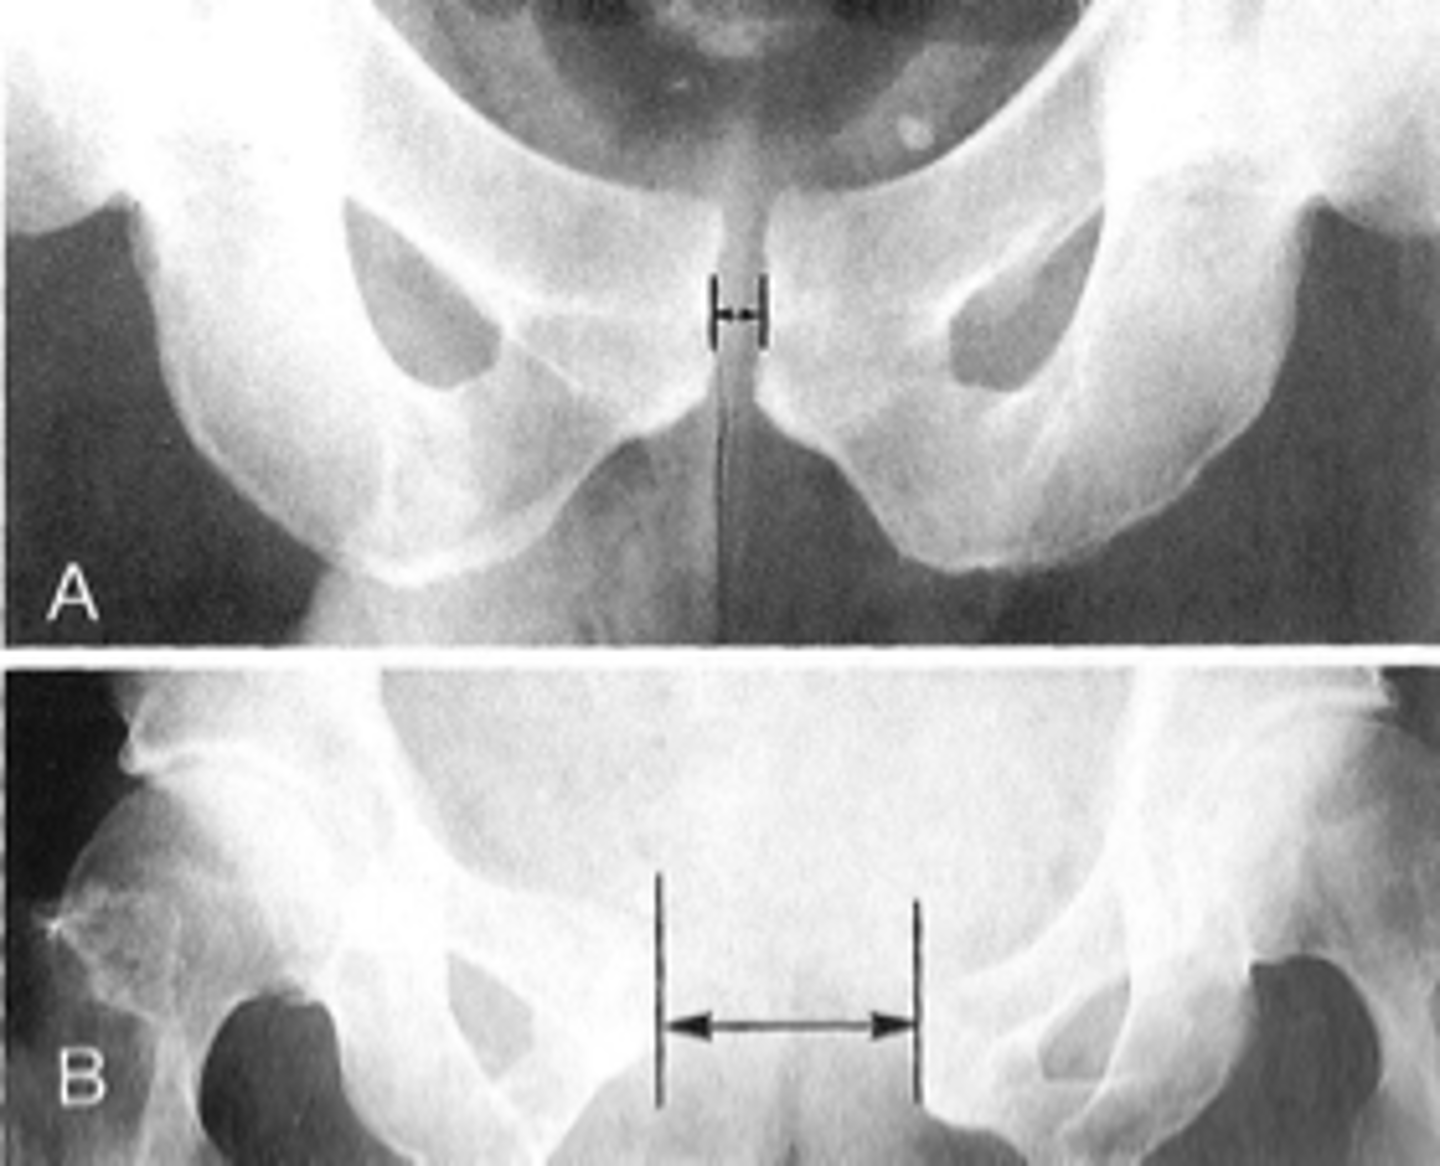

Pubic symphysis

ID 1

<p>ID 1</p>

Symphysis pubis width

ID measurement

<p>ID measurement</p>

AP pelvis

What view is used to see the symphysis pubis width?

<p>What view is used to see the symphysis pubis width?</p>

Distance between opposing articular surfaces

Symphysis pubis width landmarks

<p>Symphysis pubis width landmarks</p>

8 mm

Maximum symphysis pubis width measurement in adults

<p>Maximum symphysis pubis width measurement in adults</p>

55

New cards

10 mm

Maximum symphysis pubis width measurement in children

<p>Maximum symphysis pubis width measurement in children</p>

Pregnancy/postpartum

The symphysis pubis width may be larger in _____

<p>The symphysis pubis width may be larger in _____</p>

Diastasis

Clinical significance of a widened symphysis pubis

<p>Clinical significance of a widened symphysis pubis</p>